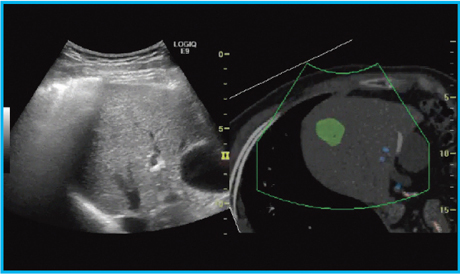

定量的なボリュームデータを取得可能な,磁気センサー搭載の超音波診断装置「LOGIQ E9」(GE社製)を用いて検討した。同装置は,他のモダリティ画像をモニタ上に同時に表示,参照することができるVolume Navigation(V-Nav)機能を搭載しており,臓器内部情報を把握し,リアルタイムなナビゲーションが可能となる(図1)。

図1 術中Volume Navigation